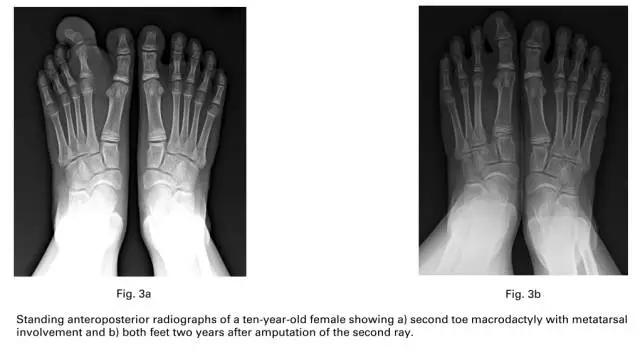

通过这些标准后,研究内包括16名患者18只足,7名男性,9名女性。平均手术年龄在46个月,6例是右足,8例是左足,2例是双足都有。巨趾影响一个足趾的是3例,2个足趾是10例,3个足趾是五例。

开始的时候我们让患者拍负重位的正位片其中有两名患者因为年纪太小无法站立拍片,测量跖趾关节的活动度,测量前足的宽度,跖趾关节平面,我们从第一和第五跖骨做垂直线,然后在跖趾关节处测量宽度,我们测量跖跗关节以远的足的面积大小,通过软件。同时我们测量对侧的正常足的宽度和面积,比较比率。用(OxAFQ-C评分表评价术前术后足的功能。因为患者年纪比较小,我们通过调查患儿父母来解决。在累积到相邻两个指头的患者,我们选择截除跖骨受累的,或者二者中间大的那个,尽量避免截除踇趾。然后截短和去脂在其他的跖列。当患者有三个指头受累的时候,我们截除中间的,然后截短和去脂在其他的两个。有一列患者在第二到第四巨趾,轴后型多趾我们截除了第三趾和第四跖列,保留了最外侧的趾体。

很多的作者报道放射状切除就可以减小前足的宽度而不需要额外的手术干预。尽管骨骼发育成熟后跖列切除的效果没有被报道,但是有报道了2例患者7年的随访后有正常的步态和穿鞋子。

在我们的研究中,手术的指正是跖骨有累及、关节僵硬或者累及多个指体,和以前B描述的那样。B和H报道了3例足部巨趾累及了多个指体,他使用了截除最大的跖列,缩短相邻的跖列,跖列转移和去脂。

跖列切除是一种减少足部体积和临床效果比较成功的方法。所有的患者术后都可以穿鞋,大部分患者术后满意。疤痕疼痛和皮肤硬结还是存在。我们建议在巨趾累及跖列、指头缺少运动、累及多个指头的可以通过跖列切除,是一种理想的方法。